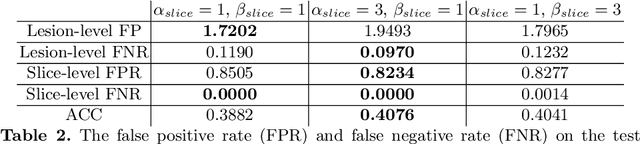

Prostate cancer (PCa) is one of the leading causes of death for men worldwide. Multi-parametric magnetic resonance (mpMR) imaging has emerged as a non-invasive diagnostic tool for detecting and localising prostate tumours by specialised radiologists. These radiological examinations, for example, for differentiating malignant lesions from benign prostatic hyperplasia in transition zones and for defining the boundaries of clinically significant cancer, remain challenging and highly skill-and-experience-dependent. We first investigate experimental results in developing object detection neural networks that are trained to predict the radiological assessment, using these high-variance labels. We further argue that such a computer-assisted diagnosis (CAD) system needs to have the ability to control the false-positive rate (FPR) or false-negative rate (FNR), in order to be usefully deployed in a clinical workflow, informing clinical decisions without further human intervention. This work proposes a novel PCa detection network that incorporates a lesion-level cost-sensitive loss and an additional slice-level loss based on a lesion-to-slice mapping function, to manage the lesion- and slice-level costs, respectively. Our experiments based on 290 clinical patients concludes that 1) The lesion-level FNR was effectively reduced from 0.19 to 0.10 and the lesion-level FPR was reduced from 1.03 to 0.66 by changing the lesion-level cost; 2) The slice-level FNR was reduced from 0.19 to 0.00 by taking into account the slice-level cost; (3) Both lesion-level and slice-level FNRs were reduced with lower FP/FPR by changing the lesion-level or slice-level costs, compared with post-training threshold adjustment using networks without the proposed cost-aware training.